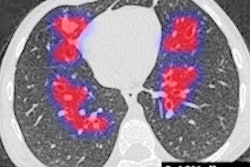

SmartCAD | COVID-19 uses Thirona's CAD4COVID-CT algorithm and Smart Reporting's COVID-19 reporting template to provide direct analysis of chest CT images and then transfers the results into a structured report.

The output includes a COVID-19 severity score on lung and lobar level, the percentage of abnormalities detected for each lobe and the lungs overall, and the percentage of lobar emphysema.